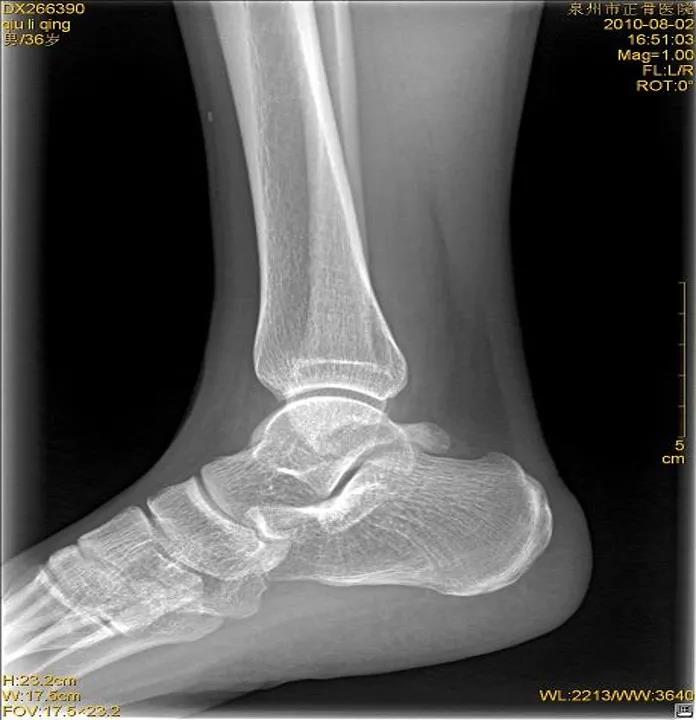

X线

踝关节正位

踝关节侧位

虽然有所防备,但有时难免发生意外。这时,患者可以先自行评估是否出现关节畸形移位或形成假关节(骨头断裂)等,如果遇到这类严重情况应固定后立即就医,如果只是局部的肿胀瘀斑,疼痛程度较低,就可以先自我急救。伤者在进行急救处理后,如有条件最好在医院进行X线或CT检查,因为小骨头的断裂或撕裂等问题并不会引起强烈的疼痛或肿胀等,但如果没有有效的医疗支具固定可能会致骨折错位或损伤进一步加剧,后期恢复不充分,还会导致陈旧性软组织受伤,在关节尤其负重部位容易引发骨关节病等慢性疾病。

X线片:基本的辅助检查(应注意某些情况并非骨折)CT:能进一步检查隐匿性骨折或撕脱性骨折MRI:可检查肌腱、韧带的损伤肌骨超声:可代替或结合MRI检查软组织的损伤